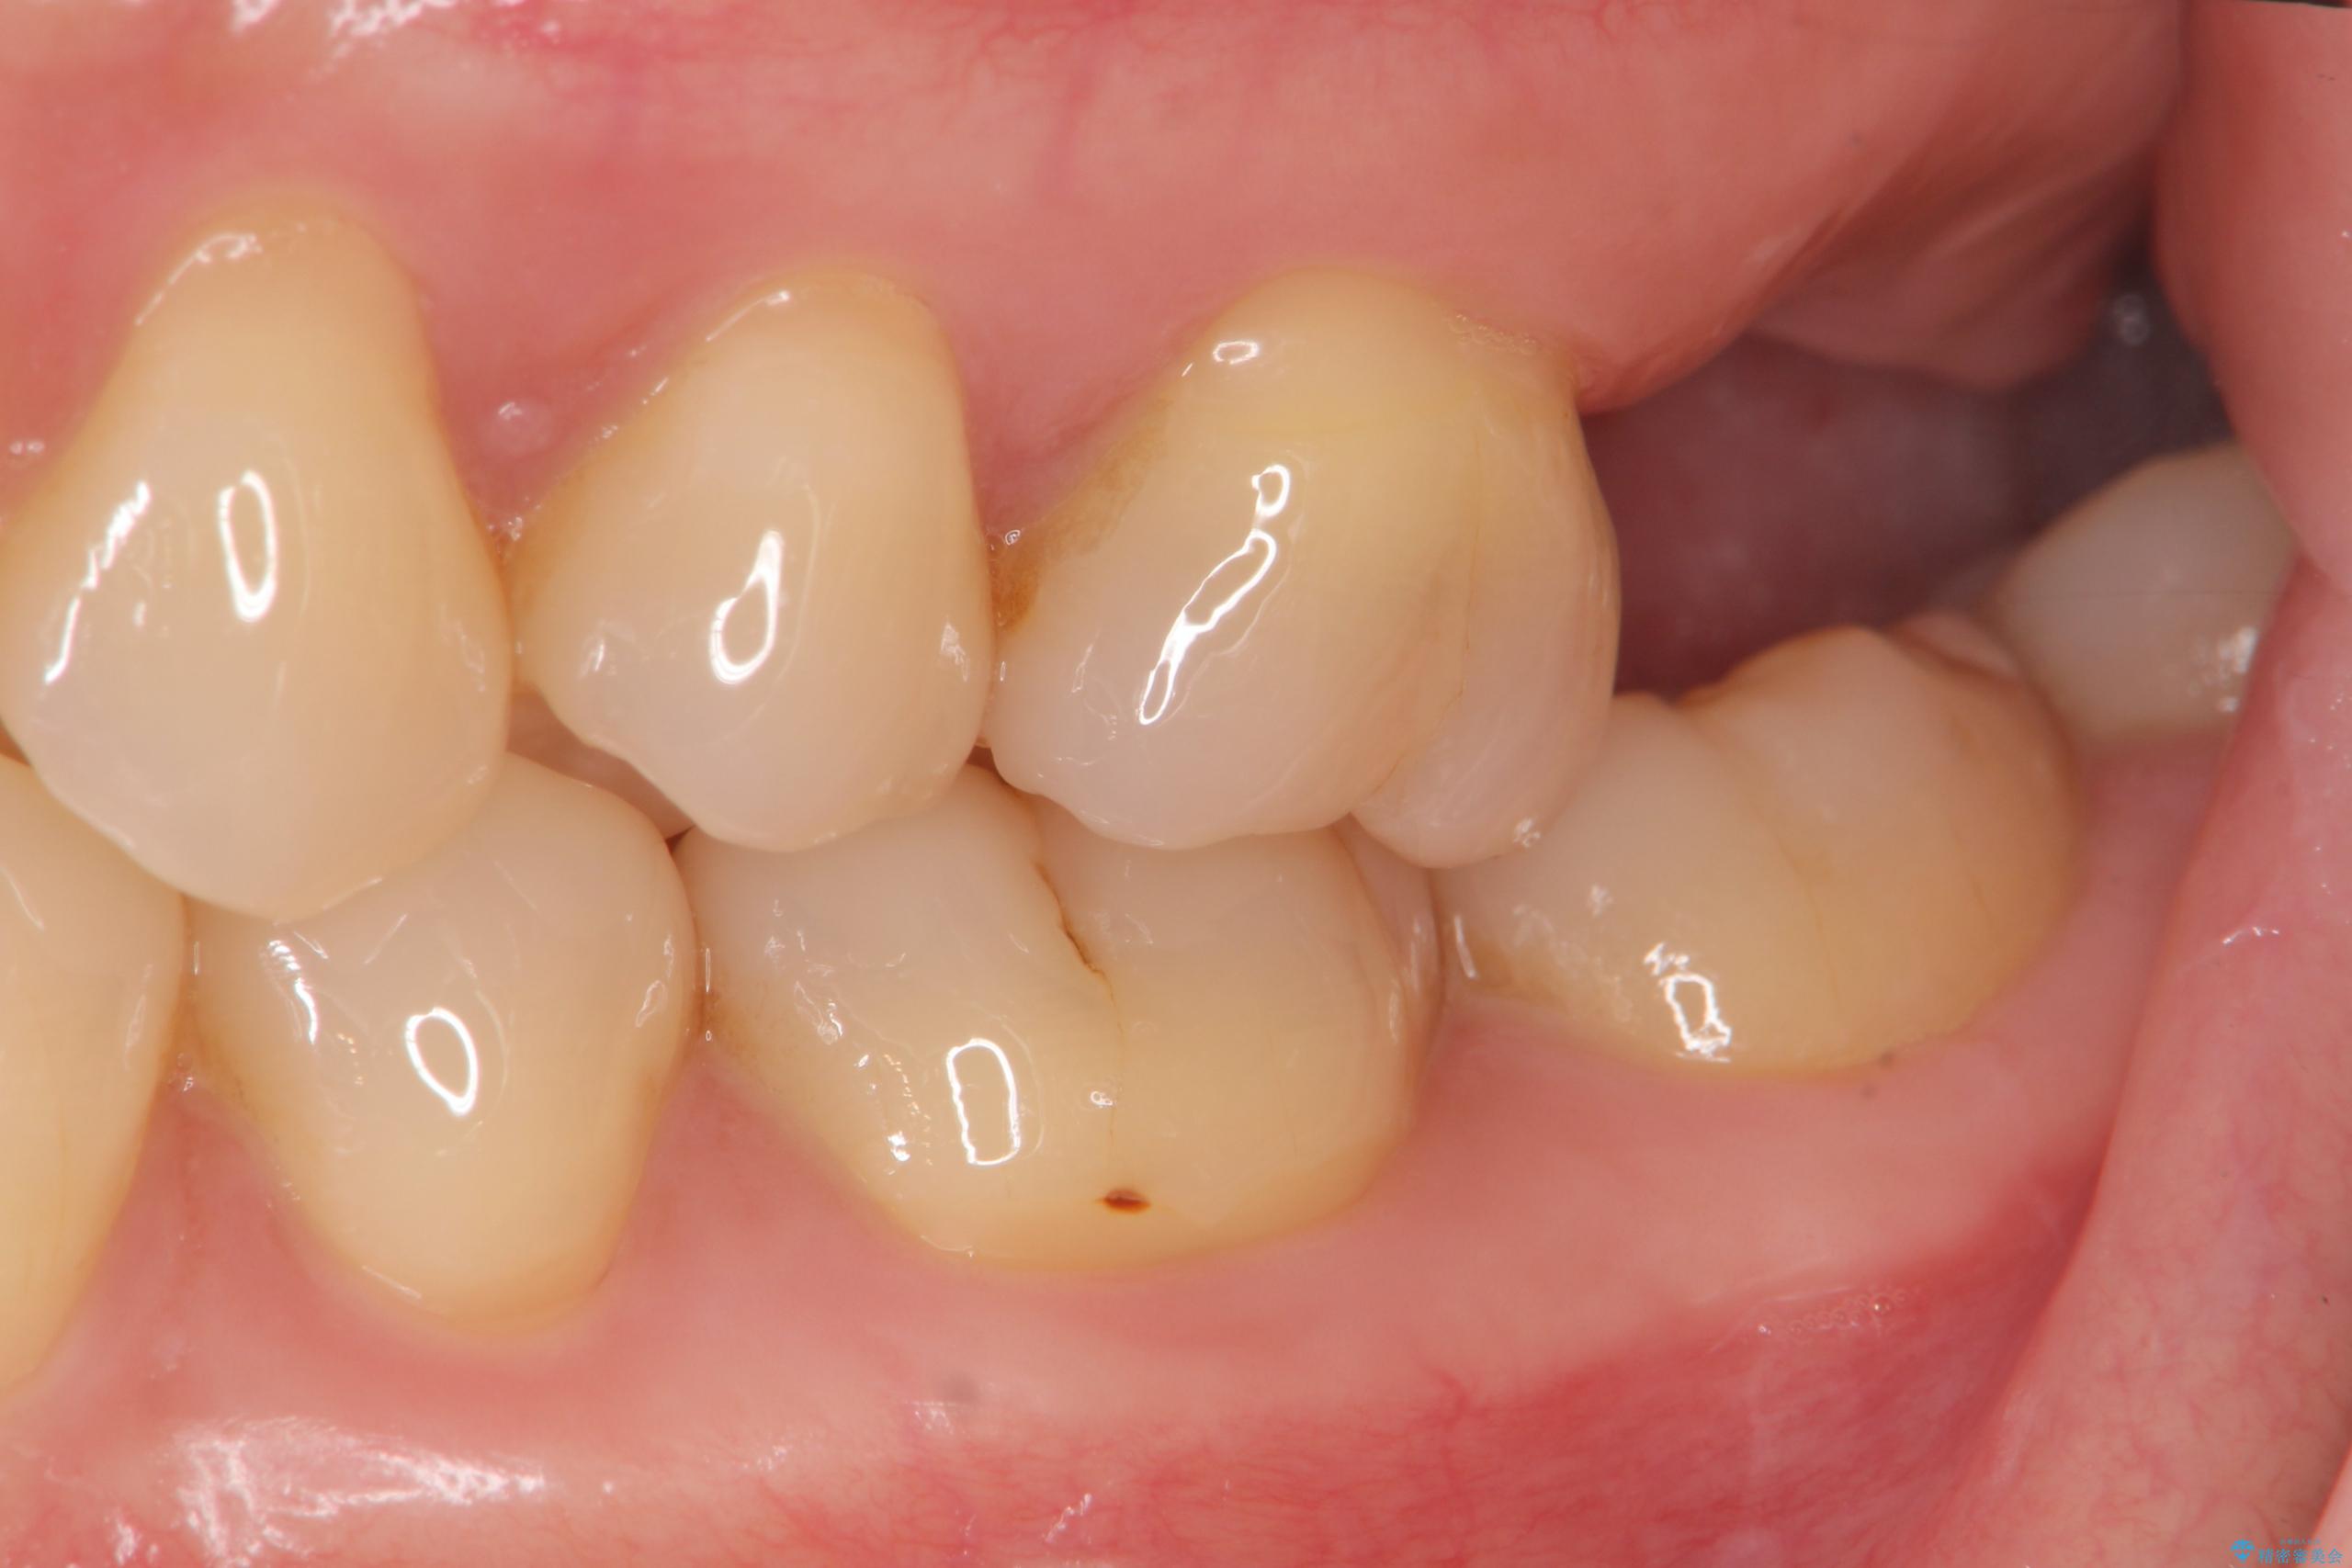

精査した結果、上顎奥歯は歯が割れてしまっており、根管治療ではなく抜歯の対象でした。

治療前

【噛むと歯が疼く】歯牙破折からのインプラント治療 治療前画像 【噛むと歯が疼く】歯牙破折からのインプラント治療 治療前画像 【噛むと歯が疼く】歯牙破折からのインプラント治療 治療前画像 【噛むと歯が疼く】歯牙破折からのインプラント治療 治療前画像 【噛むと歯が疼く】歯牙破折からのインプラント治療 治療前画像 【噛むと歯が疼く】歯牙破折からのインプラント治療 治療前画像 【噛むと歯が疼く】歯牙破折からのインプラント治療 治療前画像